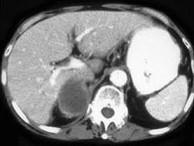

问题 男,75岁,右侧胸痛伴咯血3月余,胸部CT提示右侧中央型肺癌,请结合图像,作出诊断 ( )

选项 A、右侧肾上腺癌 B、右侧肾上腺嗜铬细胞瘤 C、右侧肾上腺转移瘤 D、右侧肾上腺腺瘤 E、右侧肾上腺囊肿

答案 C